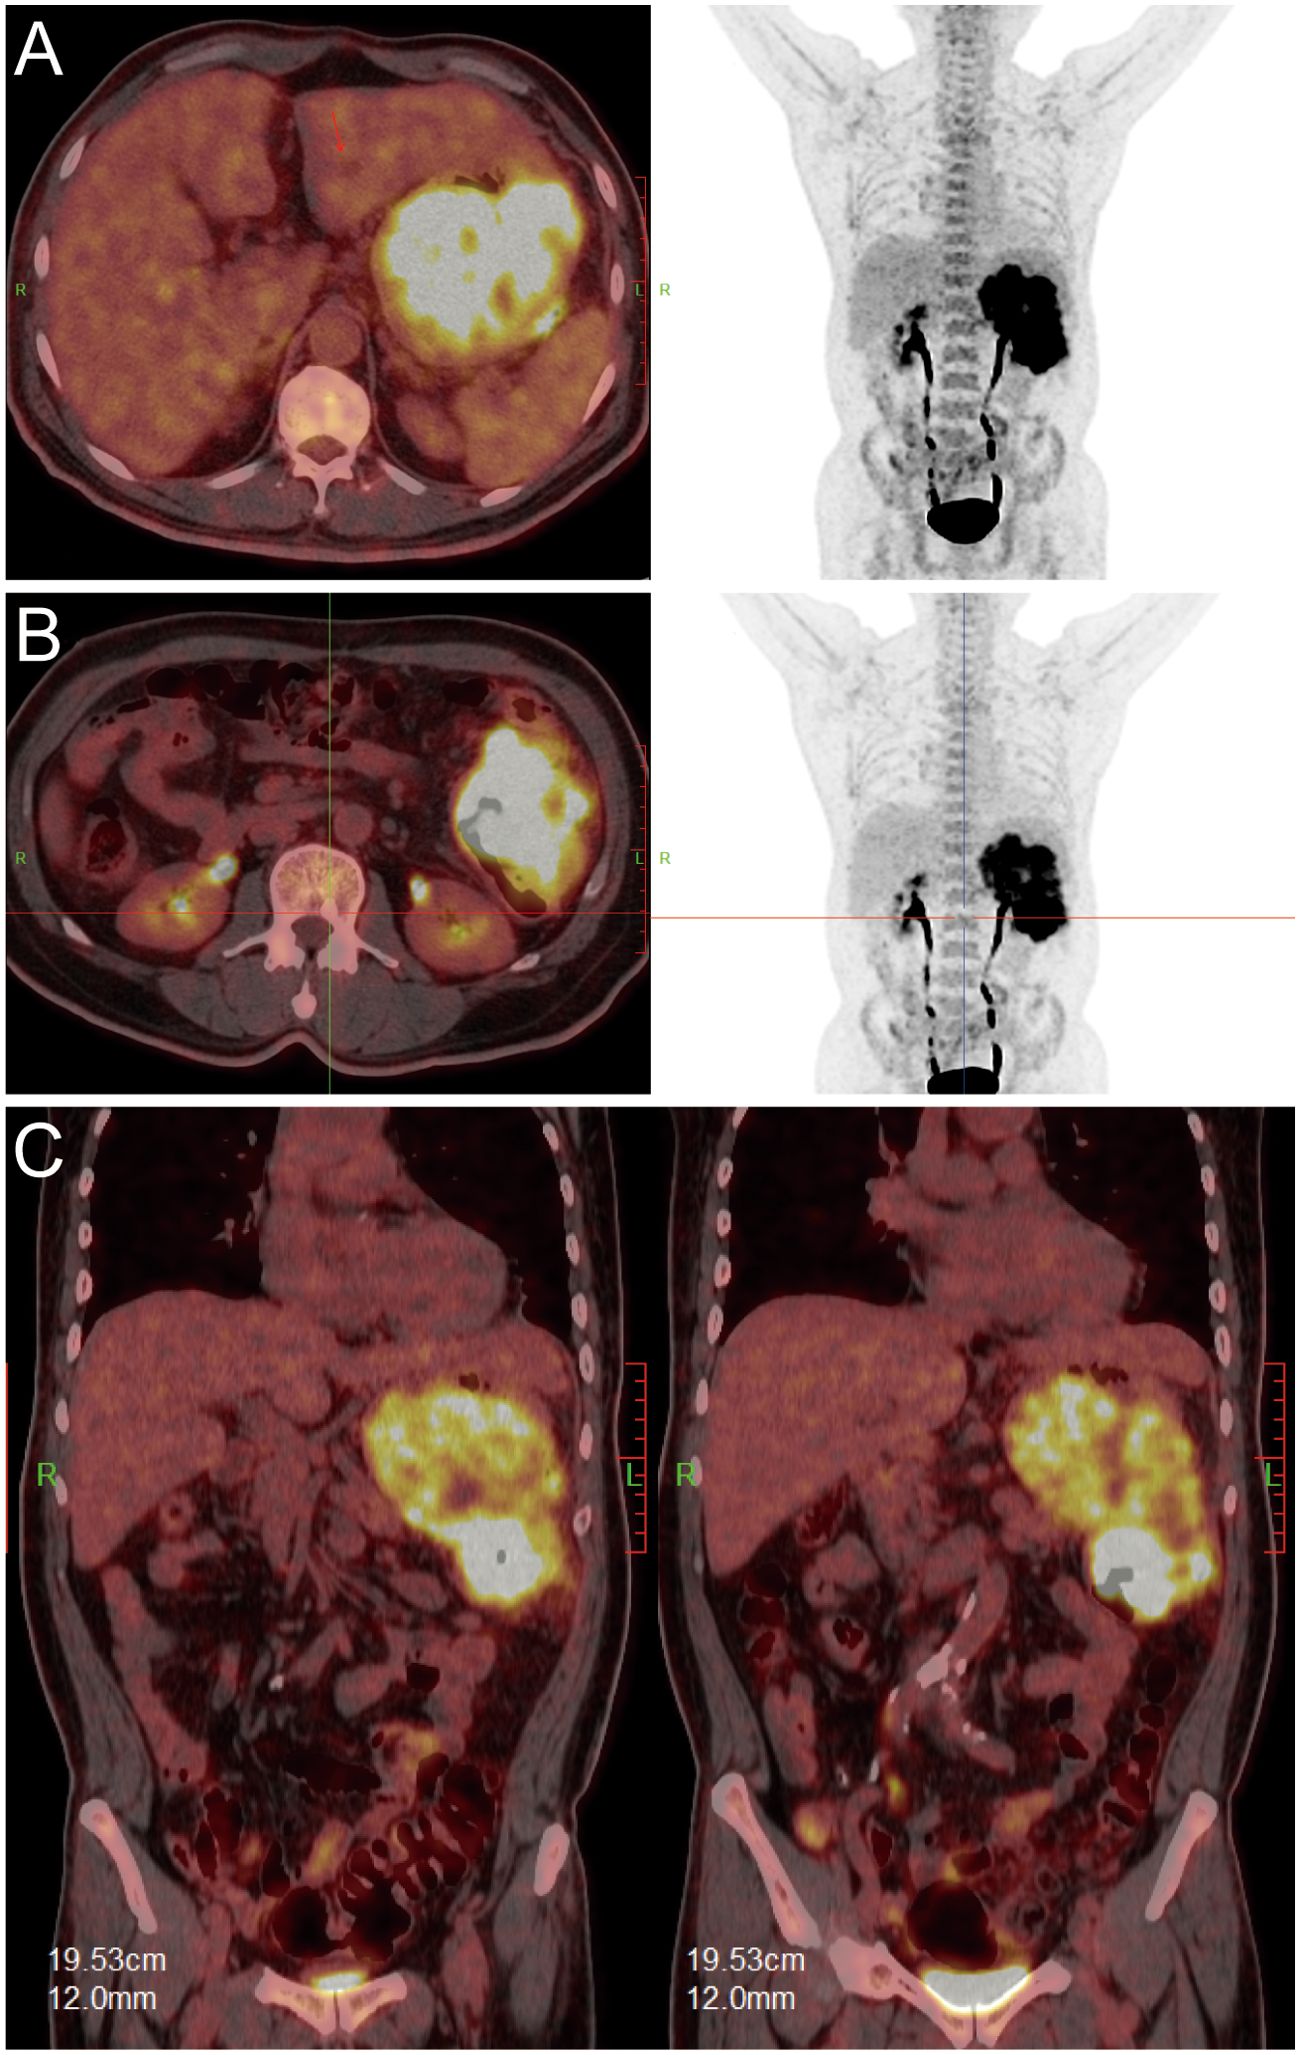

Upon transfer to our institution, multidisciplinary review noted an inconsistency: the exophytic morphology contradicted typical gastric cancer phenotypes. Moreover, the possibility of lower gastrointestinal (GI) bleeding could not be entirely ruled out. PET/CT demonstrated intense FDG avidity (SUVmax 39) in a mass bridging the gastric body and splenic flexure, with infiltration of pericolonic fat and metabolically active lymph nodes (Figure 3). Subsequent colonoscopy uncovered a protruded mass projecting into the lumen with an eroded surface at the splenic flexure (Figures 2C, D), prompting revision of the diagnosis to primary colonic malignancy with gastric invasion. What warrants particular attention and differentiation here is that, unlike typical gastric cancers characterized by ulcerative or infiltrative growth patterns originating from the mucosal epithelium with early lymphatic spread, exophytic gastric tumors demonstrate expansive growth and pathological heterogeneity. These masses may arise from submucosal tissues (e.g., GIST) or represent direct invasion from adjacent organs (e.g., colon cancer). Their intact overlying mucosa often leads to false-negative conventional biopsies, creating a diagnostic pitfall. Furthermore, their distinct biological behavior (predominantly hematogenous metastasis) and therapeutic requirements (either organ-sparing resection or multivisceral resection) necessitate precise origin determination through advanced imaging and deep-tissue sampling before intervention.

Figure 3

PET and CT scan images showing various sections of the abdomen and torso in panels A, B, and C. Panel A shows transverse views with highlighted areas indicating metabolic activity. Panel B displays similar transverse views, focusing on the abdominal region with increased metabolic activity. Panel C consists of coronal views showing vivid areas in the abdomen, suggesting areas of interest or concern.

Figure 3. PET/CT fusion images. [(A, B): axial; (C): coronal] demonstrating hypermetabolic tumor involvement of the splenic flexure (SUVmax 39).